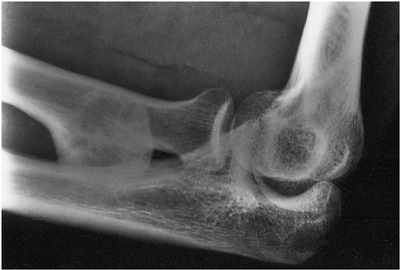

![]() |

Figure 10-26.

Ectopic bone bridging the proximal ulna and radius. The exposure of the radial tuberosity was across the periosteal surface of the ulna. |

procedure. Radial nerve injury has been reported and may be seen as

anterior modified Henry approach (4,8). Ectopic bone is a recognized complication of the two-incision technique and bridges the proximal radius and ulna (Fig. 10-26). This, however, can be minimized or avoided by not exposing the periosteal surface of the ulna with the forearm incision (Fig. 10-27) and by splitting the muscle fibers as the tuberosity is exposed (Fig. 10-28)(6).